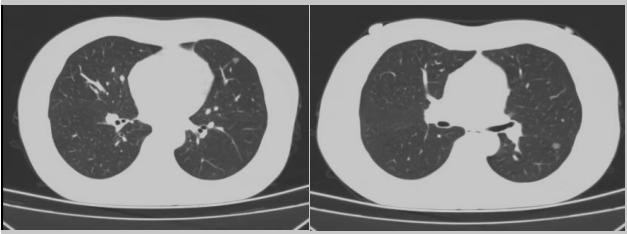

病例二:42歲的范女士,半年前體檢時發現雙側多發肺結節,平時沒有什么不適。四個月后再次復查胸部CT,左上肺及下肺多發的磨玻璃結節,其中下葉9mm的結節定為高危病灶。看到結果范女士坐不住了,多方打聽慕名找到了市二院院長王瑾,經“肺結節MDT”團隊會診后,決定手術治療。入院后,胸外科副主任醫師薛飛詳細與范女士溝通,并利用Mimics做好了術前肺部三維重建手術規劃,打消了范女士心中的顧慮。經過前期充分準備后,歷經1小時30分,完成“胸腔鏡下左肺上葉舌段楔切及左肺下葉背段切除術”,術后病理檢查結果確診為左肺微浸潤性腺癌。在胸外科團隊的悉心照顧下,患者術后恢復良好,一周后順利出院。